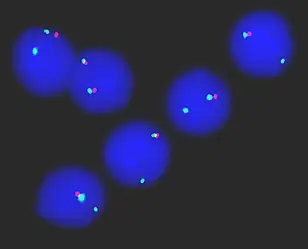

A single red signal in the nucleus of leukemia cells indicates a partial loss of chromosome 17 leading to resistance to apoptosis and chemotherapy. Picture Source: Daniel Mertens, German Cancer Research Center and University Ulm

Programmed cell death, or apoptosis, is a protective mechanism of the body to prevent cells with damaged genetic material from becoming dangerous for the whole organism. In cancer cells, however, this protective mechanism often fails and they become resistant to those signals that order them to commit suicide. This is particularly fatal, because the effective mechanism of many types of chemotherapy is to trigger apoptosis.

Legend: A single red signal in the nucleus of leukemia cells indicates a partial loss of chromosome 17 leading to resistance to apoptosis and chemotherapy